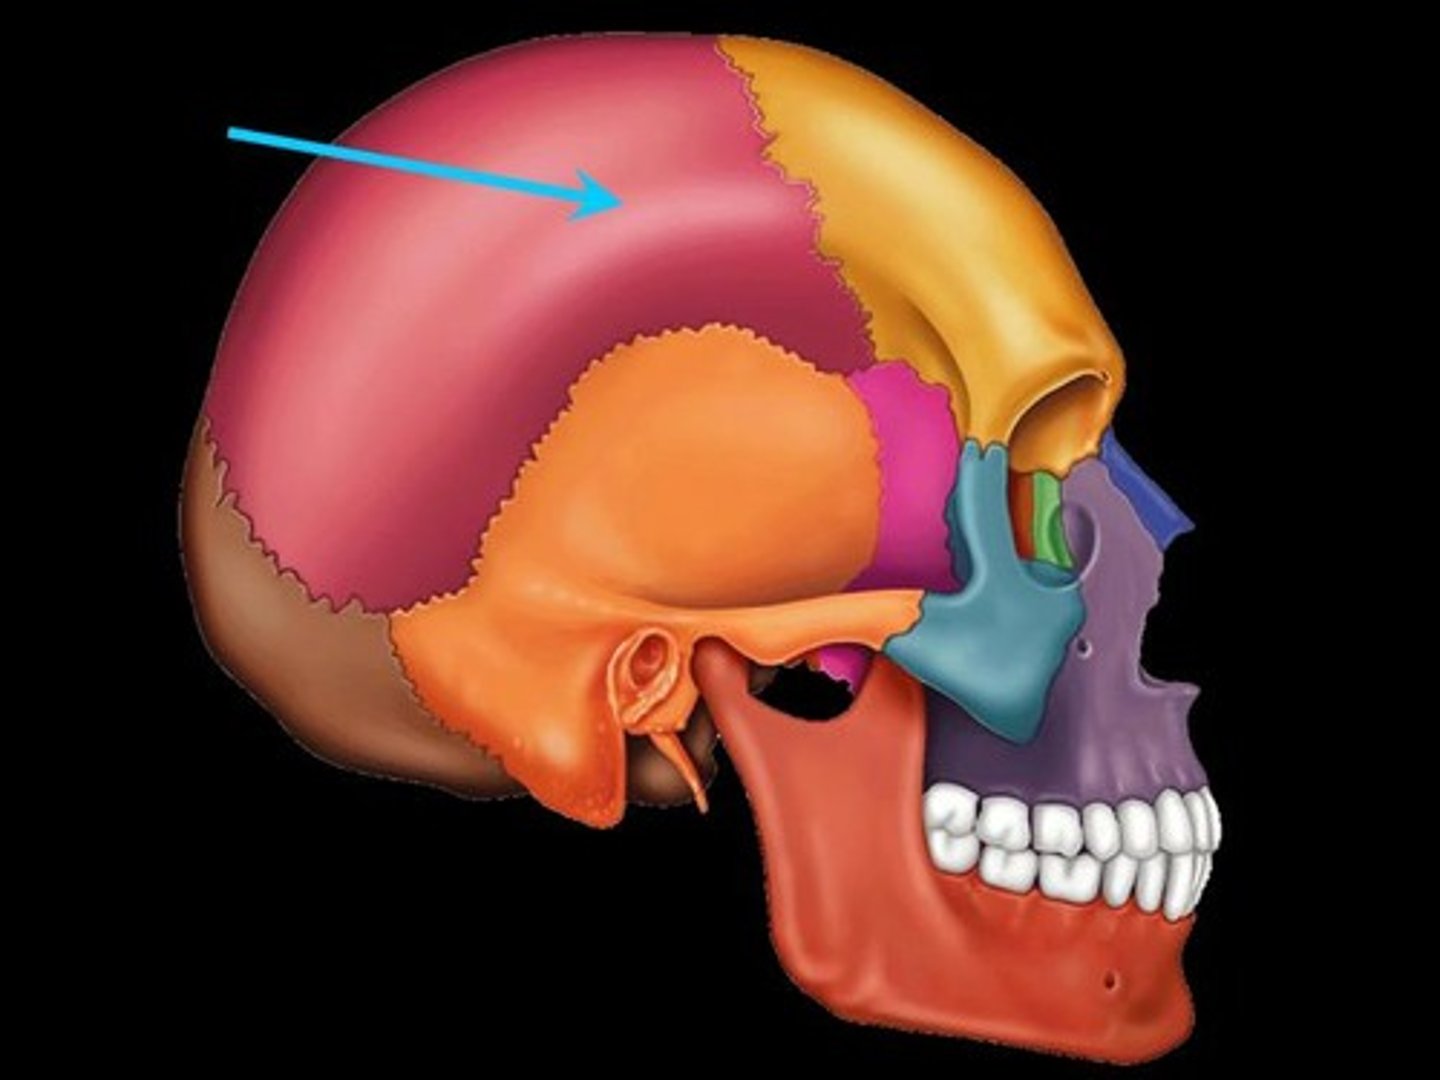

Parts of the Skull

Parietal Bone